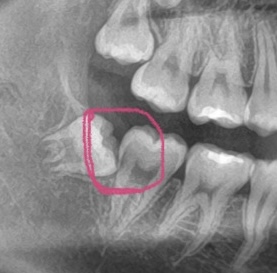

レントゲンで黒くなってるところがあるので虫歯では?と心配になりました。(赤丸のところ)

画像1IMG_3251.jpeg

バーンアウトというのですが、歯科用レントゲンでの歯頚部の濃度増減現象を指します。

これは歯頚部が、くびれているために、濃度が増強されう蝕のように映るのです。

添付されたレントゲンは親知らずと第二大臼歯間ですが、第二大臼歯がう蝕ではないかと心配されているのですよね。私見では、バーンアウトではなく,う蝕にり患しているでしょう。

この場所の虫歯の発見は目で見ても殆ど分からないと思いますよ。

また親知らずがこのように生えていると虫歯になりやすいので第2大臼歯を残したければ親知らずは抜かれた方が無難です。

もし第2大臼歯が虫歯だとこの部位の治療は困難を極めるため、予後も悪いです。

レントゲン拝見しましたが個人的にはむし歯と思います、ただ心配なさっているようなので一度診てもらってください。